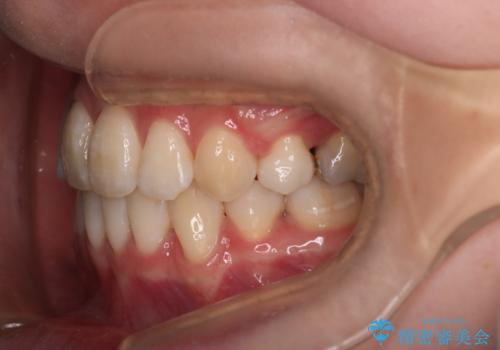

少しスペースクローズに時間がかかりましたが、MIを用いたワイヤー矯正で

主訴である出っ歯と叢生が改善されました。口も閉じやすくなり、スッキリとした口元になりました。